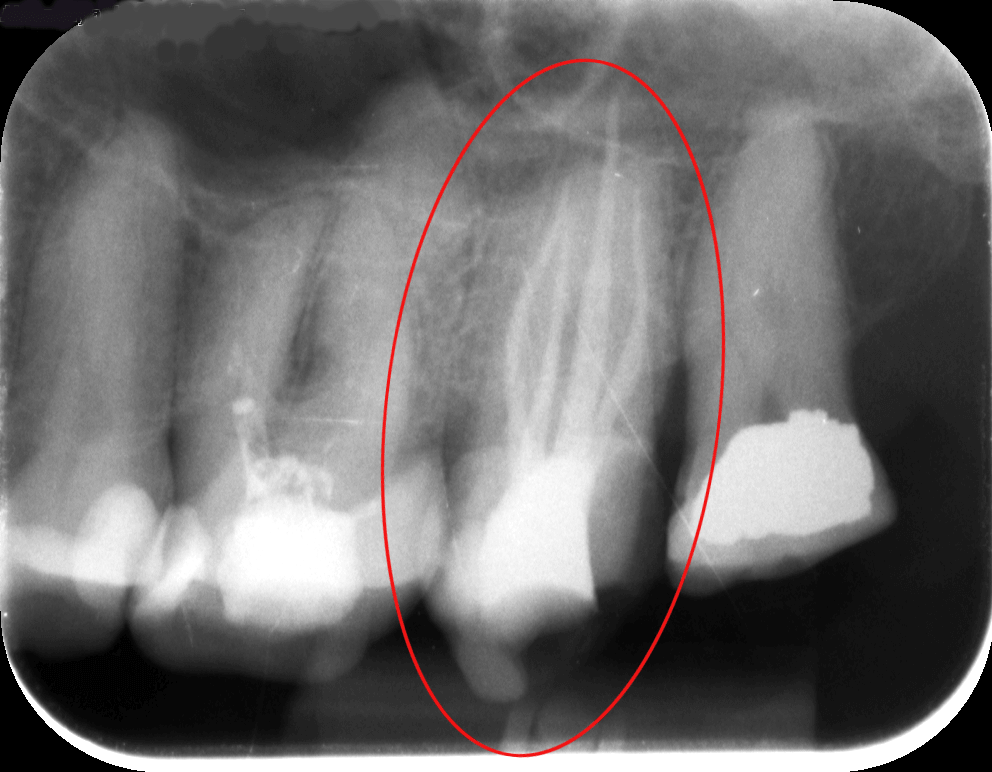

A mikroszkópos feltárás során egyértelműen kivehető volt a 4. csatorna, amit feltártunk, kitisztítottunk, így a gyökértömésről készített kontrollfelvételen (2. kép) már a 4. csatorna teljesen elkülönülő lefutását is nyomon követhetjük.

Ha nem mikroszkóppal gyökérkezelünk, akkor ennek a csatornának a megtalálására, kitisztítására elenyésző az esély, így a fog panaszos maradhat, góccá válhat, és eltávolítása előbb-utóbb indokolttá válik.